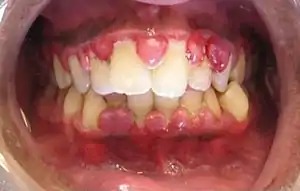

The symptoms of gingivitis are somewhat non-specific and manifest in the gum tissue as the classic signs of inflammation:

- Swollen gums

- Bright red gums

- Gums that are tender or painful to the touch

- Bleeding gums or bleeding after brushing and/or flossing

- Bad breath (halitosis)

Additionally, the stippling that normally exists in the gum tissue of some individuals will often disappear and the gums may appear shiny when the gum tissue becomes swollen and stretched over the inflamed underlying connective tissue. The accumulation may also emit an unpleasant odor. When the gingiva are swollen, the epithelial lining of the gingival crevice becomes ulcerated and the gums will bleed more easily with even gentle brushing, and especially when flossing.